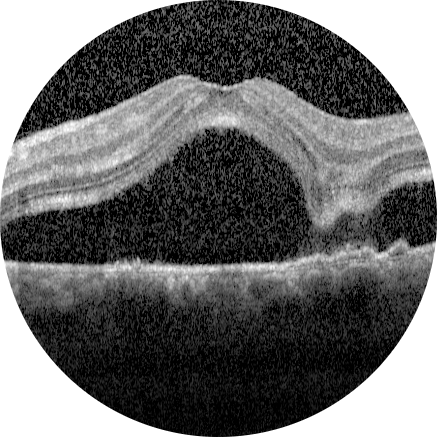

Sağ gözde beş gündür artan görme azlığı olan 30 yaşındaki kadın hastanın renkli ...